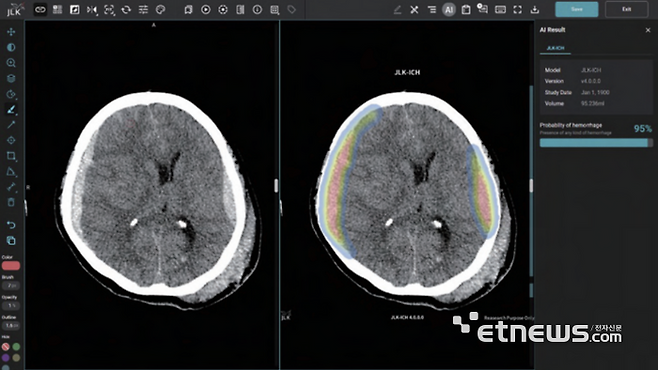

20일(현지시간) 홍콩 사우스차이나모닝포스트(SCMP)에 따르면 중국 저장성에 사는 왕 모(67) 씨는 최근 야외에서 두 시간 동안 햇볕을 쬐다가 뇌출혈 증세를 보이며 쓰러졌다. 왕 씨는 '등을 햇볕에 노출하면 양기를 보강하고 습기를 없애 질환 치료에 도움이 된다'는 중국 전통 요법을 따르던 중이었다.

왕 씨는 곧바로 저장성 인민병원으로 이송돼 동맥류 뇌출혈 진단을 받고 긴급 수술을 받았으나, 한때 혼수상태에 빠지며 위태로운 상황을 겪었다.